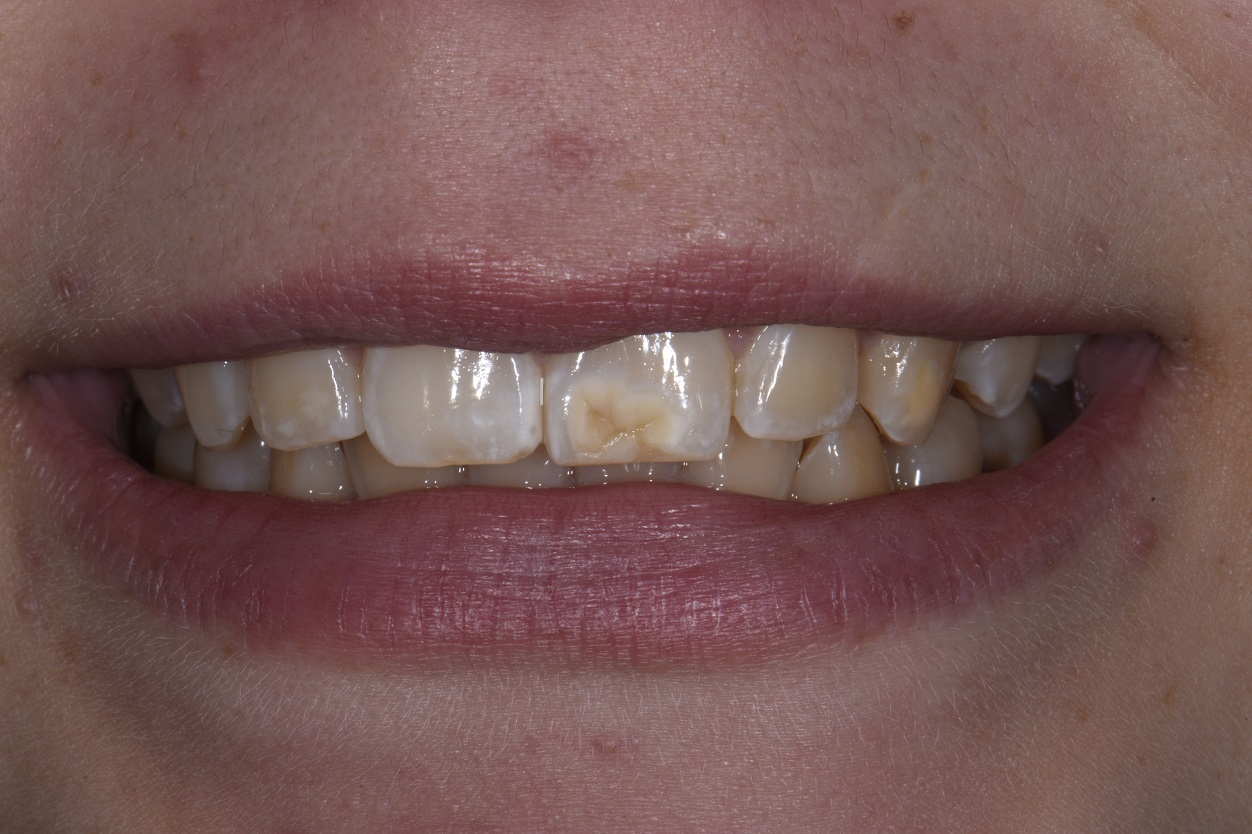

From smiledentallounge.com

ICON Resin Infiltration The Smile Dental Lounge Dental Clinic Johor Where Is Resin Infiltration Most Successfully Used They were informed that the process may need to be repeated several times in order to treat deeper lesions. resin infiltration is a minimally invasive technique to treat mild hypomineralized lesions. the principle of resin infiltration is to perfuse the porous enamel with resin by capillary action, thereby arresting lesion. resin infiltration seems to be a clinically. Where Is Resin Infiltration Most Successfully Used.